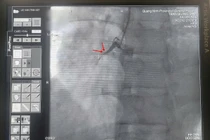

Thuốc tiêu sợi huyết điều trị đột quỵ thiếu máu não cấp, giúp tan cục máu đông, tái thông dòng máu lên não, hạn chế tổn thương nhu mô não, giảm nguy cơ tàn phế.

Sử dụng thuốc tiêu sợi huyết là phương pháp đem lại hiệu quả cao trong điều trị nhồi máu não cấp nhưng chỉ áp dụng cho bệnh nhân trong vòng 4,5 giờ đầu, tính từ thời gian khởi phát bệnh. Vì vậy, cần đến viện sớm.